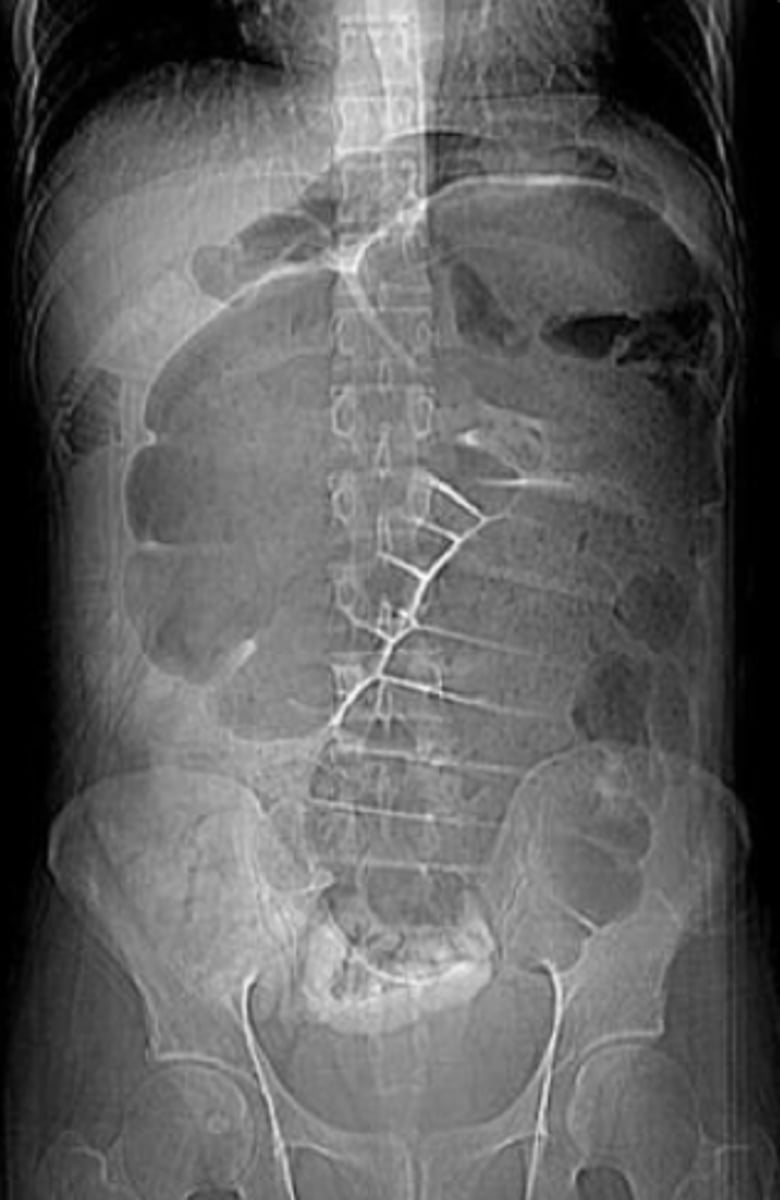

Sigmoid Volvus

Dx: Plain film x-ray (low specificity): U shaped, bent inner tube

-> Abd CT scan

-> Contrast enema

RF: Long-term care facility

-> Older age

-> Bed ridden

-> Chronic constipation

Clinical: Insidious onset of abdominal pain

-> Abdominal distention

-> Nausea, Vomiting, Constipation

Management

- Flexible sigmoidectomy (to reduce volvulus)

-> Surgery (to prevent recurrence)